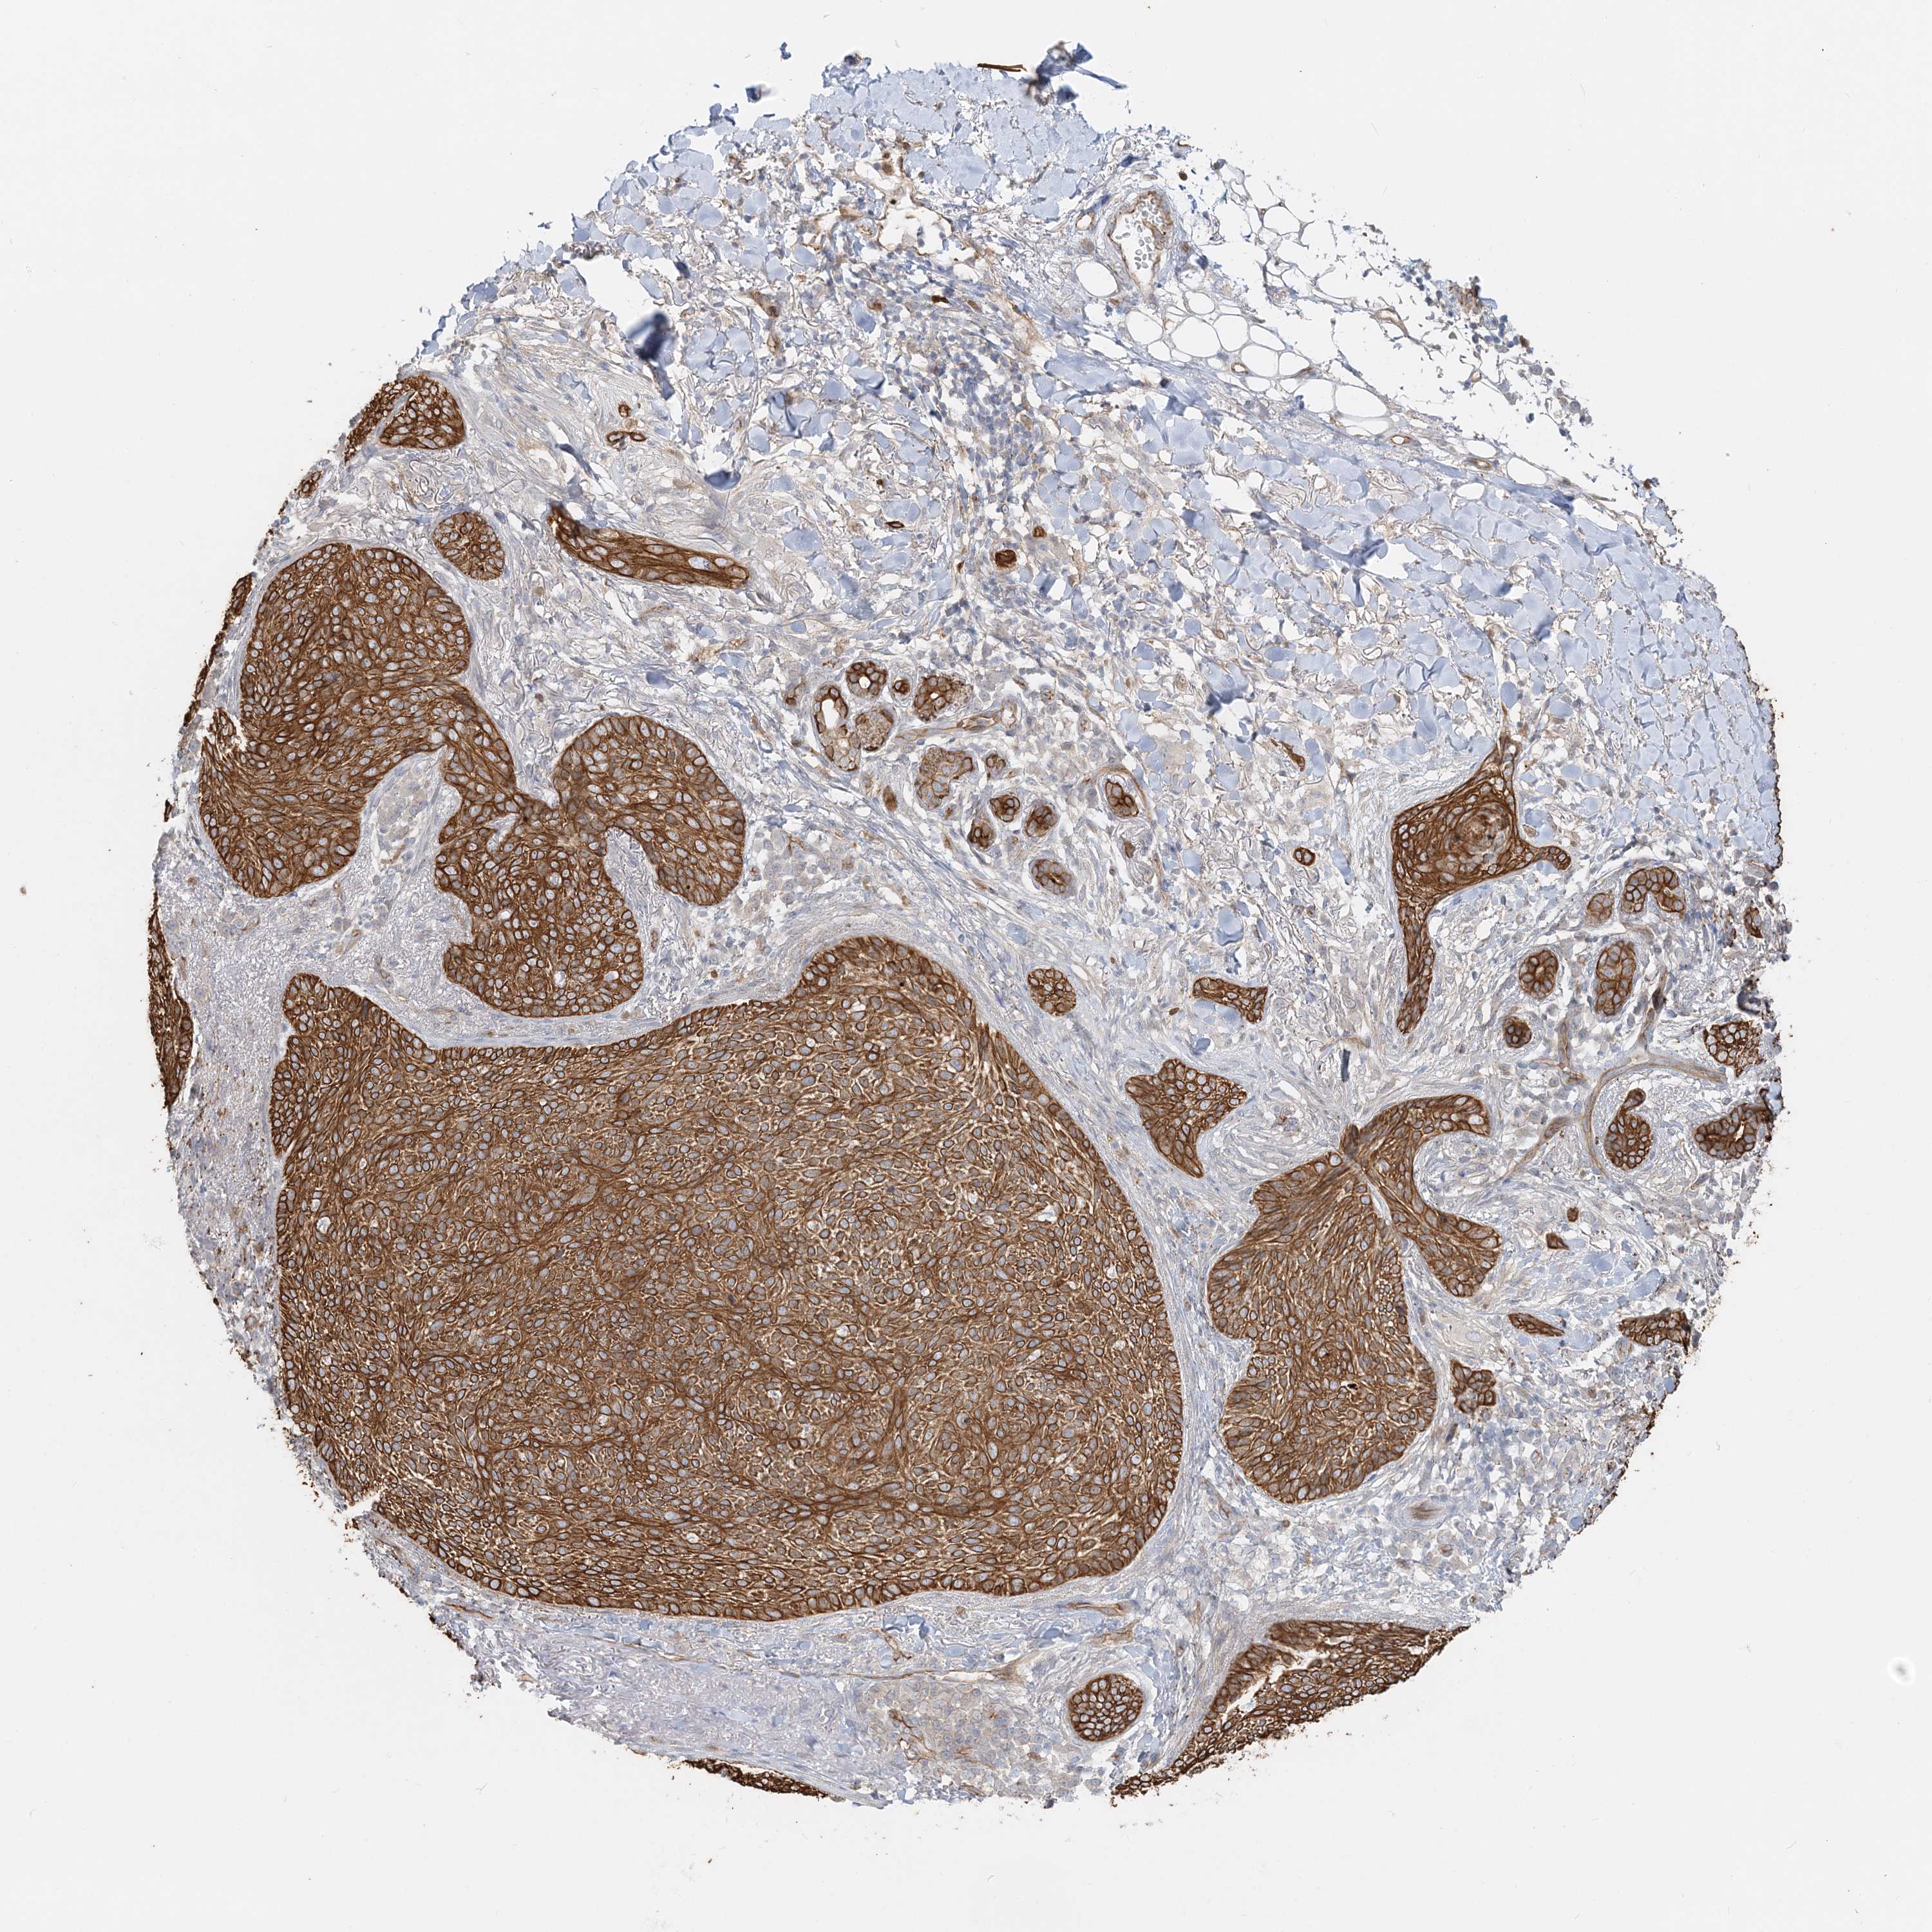

Basal cell and squamous cell cancer

SKIN CANCER - Protein expressioni

A mouse-over function shows sample information and annotation data. Click on an image to view it in a full screen mode. Samples can be filtered based on level of antibody staining by selecting one or several of the following categories: high, medium, low and not detected. The assay and annotation is described here.

Antibody stainingi

Antibody staining in the annotated cell types in the current human tissue is reported as not detected, low, medium, or high, based on conventional immunohistochemistry profiling in selected tissues. This score is based on the combination of the staining intensity and fraction of stained cells.

Each image is clickable and will lead to virtual microscopy that enables deeper exploration of all samples and also displays staining intensity scores, fraction scores and subcellular localization as well as patient and tissue information for each sample.

Antibody HPA036805

Antibody HPA036806

Staining

High

Medium

Low

Not detected

Intensity

Strong

Moderate

Weak

Negative

Quantity

>75%

75%-25%

<25%

None

Location

Nuclear

Cytoplasmic/membranous

Cytoplasmic/membranous,nuclear

Basal cell carcinoma

Squamous cell carcinoma, NOS

Squamous cell carcinoma, metastatic, NOS